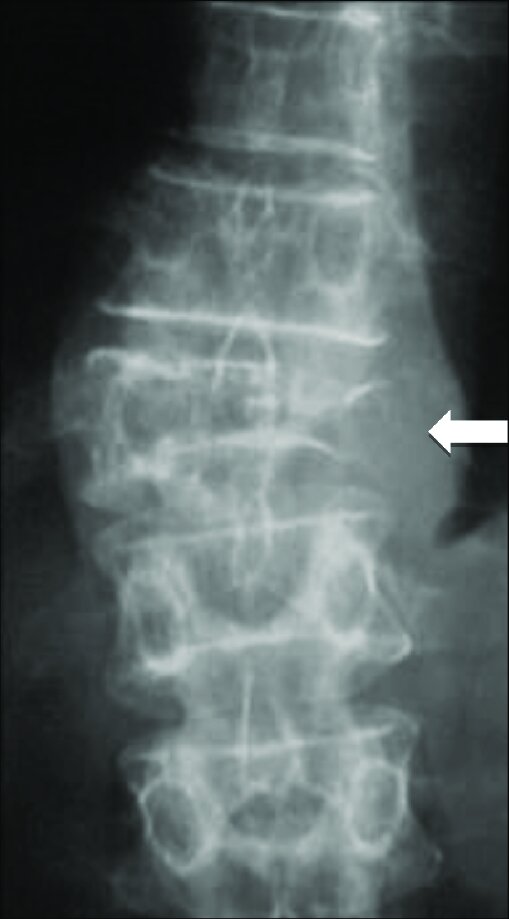

Lumbar spine – anterior-posterior view

Osteolytic lesion with cortical breakthrough and collapse of L3 vertebrae. Adjacent soft tissue mass is present.